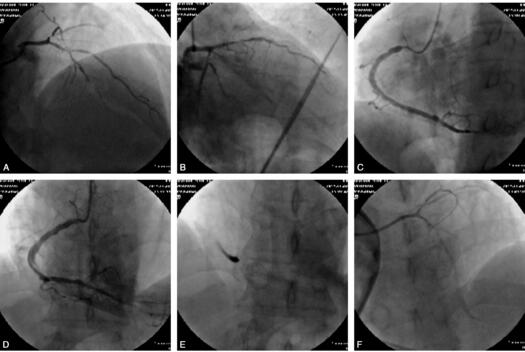

查体:血压112/70mmHg心率82次/分,律不齐,可及期前收缩,大于8次/分,各瓣膜未闻及杂音。双下肢无水肿。实验室检查:CK 6241U/L、CK-MB51U/L;肌钙蛋白1730pg/ml。纤维蛋白原4.6g/L高密度脂蛋白0.77mmol/L,低密度脂蛋白3.37mmol/L。入院心电图显示:Ⅰ、avL、V1~V4导联ST段压低≥0.5mV T波倒置。诊断:冠心病,急性非ST段抬高心肌梗死KillpⅠ级。因患者转入后给予冠心病药物强化治疗,症状缓解,生命体征平稳,故药物治疗10天后行冠脉造影检查。CAG结果:左冠造影,左主干未见明显狭窄,LAD近段95%节段性狭窄;LCX近段分叉处90%狭窄,远端闭塞,第一钝缘支近段80%狭窄,前向血流2级;以6FJR4.0造影导管行右冠造影:右冠开口90%狭窄,在行右冠造影过程中,患者突然出现胸痛,心电监测示下壁ST段抬高,血压、心率进行性下降,造影显示近中段夹层,血流消失;立即给予多巴胺、阿托品等药物,并置入IABP,同时立即开通闭塞前降支以改善心肌供血,以EBU3.5指引导管至左冠口,用MV1.5mm×15mm球囊过闭塞处予以扩张,前向血流TIMI1级,此时患者突然出现阿-斯发作。心电监测:室颤。意识丧失,立即给予电除颤,多巴胺升压,并再次给冠脉内推注替罗非班、腺苷等药物积极抢救,造影前降支血流TIMI1级,同时气管插管,给升压、扩冠、纠正酸中毒等药物治疗,并持续心外按压等抢救,终因抢救无效死亡。造影见图3。

图3 A、B.LAD近段95%节段性狭窄,第一对角支开口90%狭窄,LCX近段分叉处90%以上狭窄、远端闭塞;C~E.右冠造影致右冠近中段夹层,血流消失;F.导丝过前降支并以球囊扩张